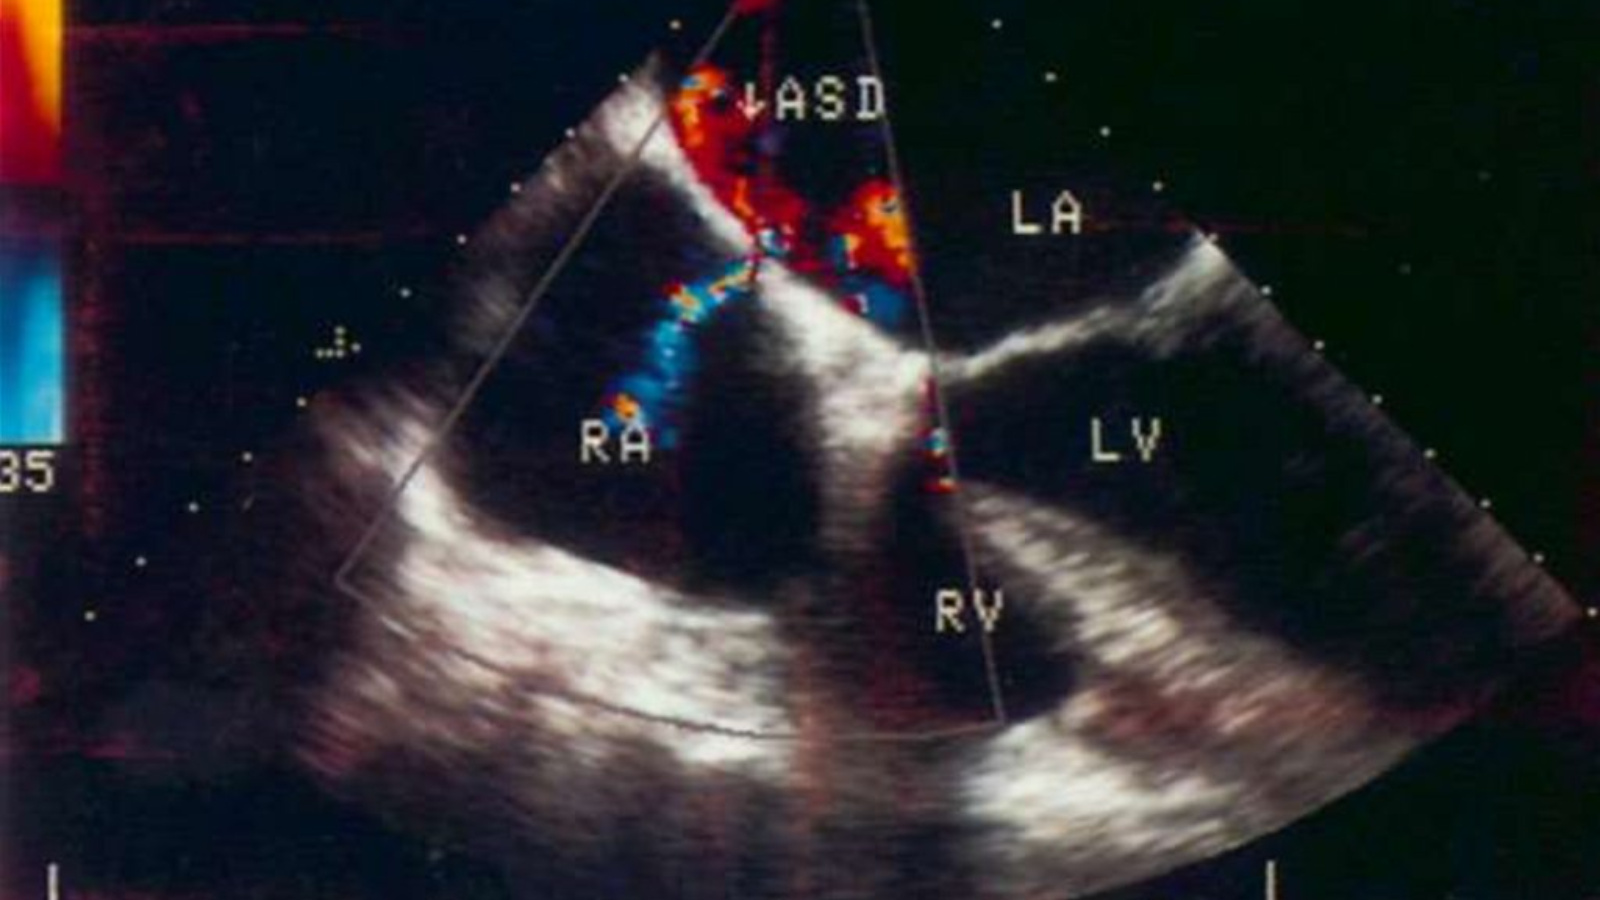

ВПС — это структурные дефекты сердца или крупных сосудов, формирующиеся на 3–8 неделе беременности, когда закладываются органы плода. Они делятся на цианотические (с посинением кожи из-за нехватки кислорода) и ацианотические (без выраженного посинения). Самые частые у новорожденных: дефект межпредсердной перегородки (ДМПП, 25–30%), дефект межжелудочковой перегородки (ДМЖП, 20–25%), открытый артериальный проток (10%) и коарктация аорты (5–7%).

Основной метод — УЗИ сердца плода на 18–22 неделе беременности (эхокардиография), выявляющее 90% пороков. После рождения: пульсоксиметрия (проверка сатурации кислорода), ЭКГ, ЭхоКГ и рентген. В России скрининг обязателен в роддомах. Диагностика заболеваний сердечно-сосудистой системы на ранних этапах и предотвращение их осложнений проводится с помощью диспансеризации и регулярных профилактических осмотров – необходимо обязательное посещение врачей согласно установленному графику и выполнение врачебных рекомендаций и указаний.